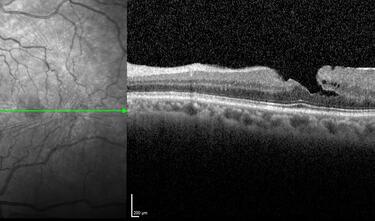

Clase 21 - Desprendimiento de vítreo y desprendimiento de retina

Clase 20 - Signos clave en patología traccional vítrorretiniana

Clase 15 - Depósitos y signos específicos en DMAE no neovascular